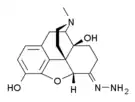

Hydrazones

Structures

| Hydrazones | ||||

|---|---|---|---|---|

Oxymorphazone Oxymorphazone | ||||